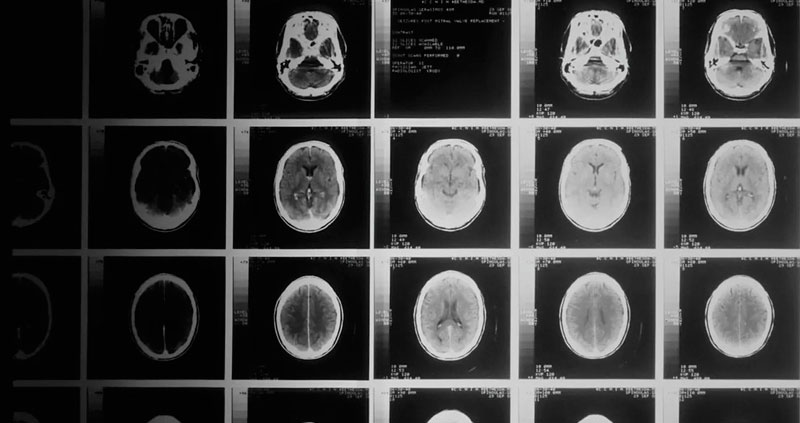

Un equipo de científicos de la Universidad Johns Hopkins, EE.UU., desarrolló recientemente un novedoso gel para administrar medicamentos, y gracias al cual curaron a todos los ratones afectados por un agresivo cáncer cerebral. Este resultado experimental ofrece una nueva esperanza para los pacientes diagnosticados con glioblastoma, uno de los tumores cerebrales más mortales y comunes en humanos.